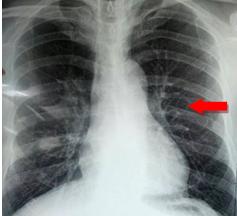

2、 肺部炎症患者

肺炎常见大叶性肺炎和支气管肺炎。大叶性肺炎起病急,胸片可见肺部纹理增粗,联结呈斑片状,位置不定。重度患者可见大片状阴影,甚至全肺布满阴影,肉眼见胸片中全肺变白。当感染得到控制,肺部阴影密度将逐渐降低,片状阴影逐步消散至条索状,直至吸收。

支气管肺炎多见于儿童、老年人及体质低下患者,常见支气管周围肺纹理增强、模糊,多延气管走向分布,严重者条索状影可融合成斑片、大片状阴影。